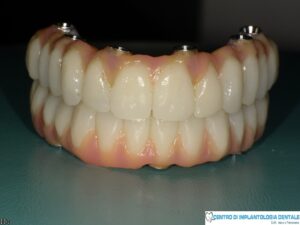

Nel nostro Centro di Implantologia Dentale abbiamo importato questa tecnica, ormai così consolidata che riporta consensi positivi a livello mondiale, personalizzandola con l’aggiunta di due impianti nell’arcata superiore (realizzando una arcata dentaria di 12 denti sostenuta da 6 impianti)

e un impianto nell’arcata inferiore (realizzando una arcata dentaria di 12 denti sostenuta da 5 impianti).

Nel nostro Centro abbiamo scelto di utilizzare un numero superiore di impianti rispetto alla tecnica di Malò in modo da assicurare nel tempo una maggiore affidabilità e durata degli impianti così sottoposti ad un carico masticatorio di 12 denti (come nostro protocollo testato). La personalizzazione della tecnica è stata eseguita a diversi livelli, che vanno dalla progettazione tecnologica dell’intervento, al controllo totale della sintomatologia intra e post operatoria, alla guida alimentare post chirurgica e alla educazione del paziente alle nuove tecniche di igiene orale.

(Tutto nella stessa giornata)L’utilizzo della protesi provvisoria programmata e realizzata precedentemente che calza alla perfezione con gli impianti inseriti, fa si’ che il paziente in poche ore possa modificare la propria bocca ed uscire dal Centro con nuovi denti fissi che garantiscono il ripristino delle funzioni masticatorie, delle condizioni estetiche e psicologiche. fig.53.